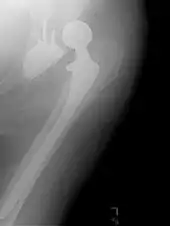

![]() An X-ray showing a left hip (right of image) that has been replaced, with the ball of this ball-and-socket joint replaced by a metal head that is set in the femur and the socket replaced by a cup | |